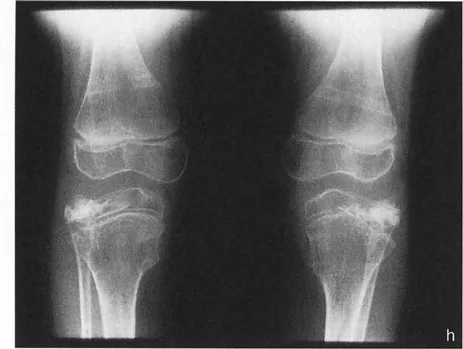

- مرض بلونت (تقوس الساق): في مرض بلونت الشديد لدى الرضع أو المراهقين، تتميز الحالة بانخفاض شديد وميل إنسي للهضبة الظنبوبية الإنسية. إذا رسمت الخطين، فإن خطي الهضبة الإنسية والوحشية يكونان بزاوية حادة بالنسبة لبعضهما البعض، ويتقاطعان بالقرب من مركز الركبة. وهذا يخلق دفعاً تقوسياً شديداً أثناء المشي.

- متلازمة إليس-فان كريفيلد (خلل التنسج الغضروفي الجلدي): تؤدي هذه الحالة الوراثية إلى انخفاض "متدرج" مميز في الهضبة الظنبوبية الوحشية. ومن المثير للاهتمام أن خطي الهضبة غالباً ما يظلان متوازيين لبعضهما البعض، لكنهما يقعان على مستويات أفقية مختلفة تماماً، مما يخلق فرقاً كبيراً في المستوى وتشوهًا شديدًا في وضعية الركبة (valgus).